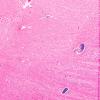

NEOPLASMS (HEMATOLYMPHOID)

Granulocytic Sarcoma